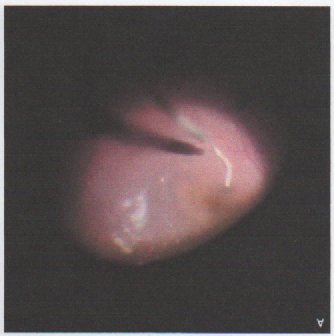

was normal. A picture of the fundiscopic examination is shown below.

DIAGNOSIS: Ocular Gnathostomiasis. On fundoscopy, a worm was seen moving sluggishly

in the posterior segment of his left fundus. A pars plana vitrectomy was performed

with removal of the worm. Under light microscopy, a larval-stage nematode with a cephalic

bulb, thick cuticle, and well-developed intestine was identified (image on right),

features consistent with Gnathostoma spinigerum. Computed tomography of the brain, orbits, chest, abdomen, and pelvis was unremarkable.